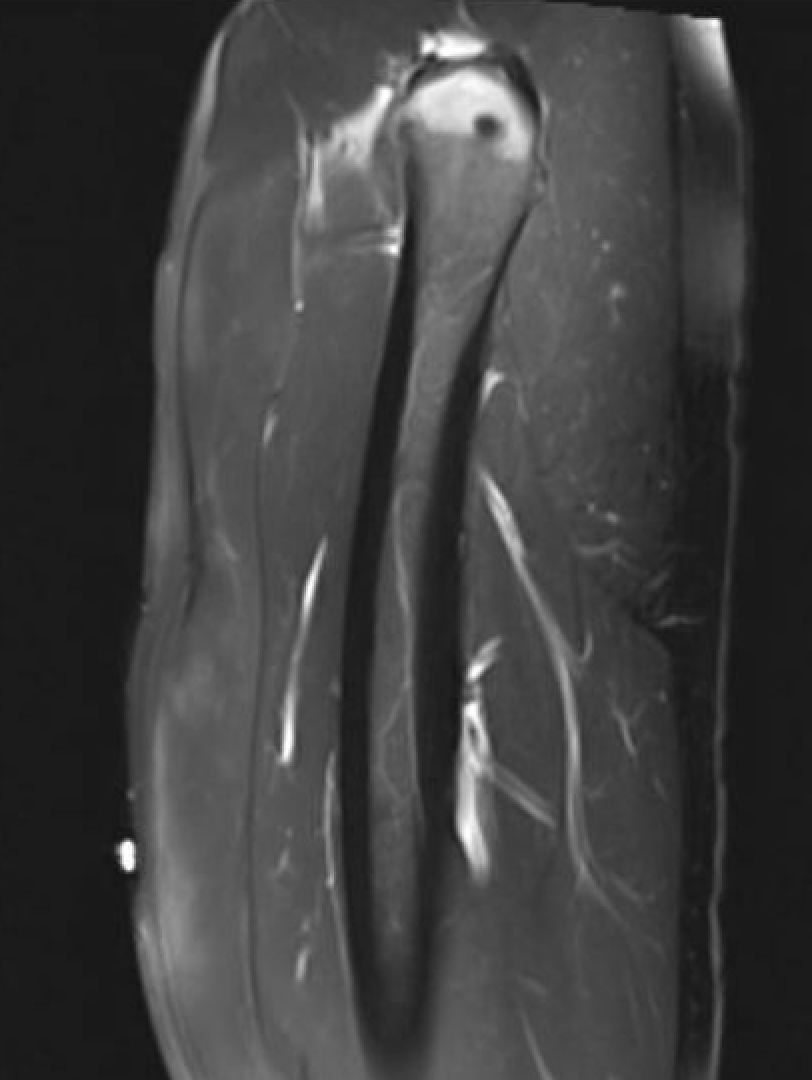

Grade 2B proximal rectus femoris muscle

Grade 3B proximal rectus femoris muscle